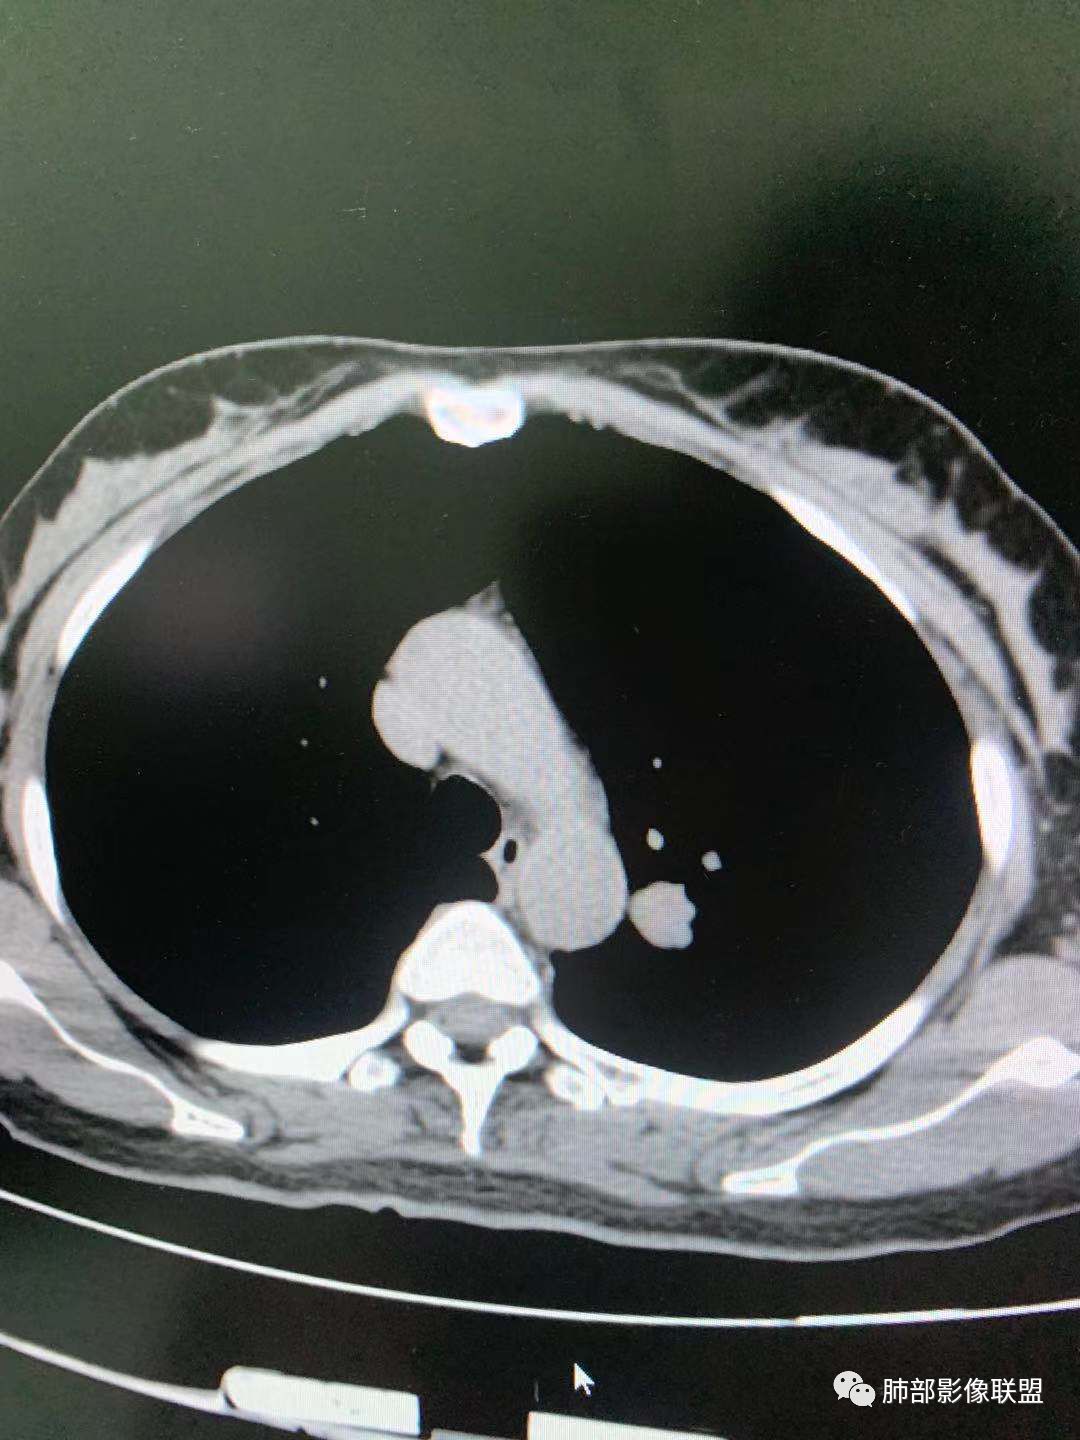

一.尖后段高密度大结节:

1.左肺上叶尖后段较大类圆形实性密度结节影,密度均匀,中等程度强化。

2.实性密度区边缘相当清楚,表面欠光整,偶见毛刺、棘突和旁出血管结构,未见典型的深分叶及邻近胸膜凹陷。

3.可疑支气管进入受阻。可惜缺乏连贯图像或冠矢状位以资判断。

4.病灶与胸膜之间有连线,邻近段支气管及肺血管整体后移,提示病灶还是有一定收缩性。

如上,单就这实性结节,硬化性肺细胞瘤(PSP)和腺癌似乎都能够解释,形态太规整了一些。

5.病灶周围见边界清楚的磨玻璃影,有点醒目,有点意外!

这是无论如何不能忽视的征象!

这点强烈提示,要么整个病灶恶性(腺癌),要么良性病灶旁滋生恶性病灶。

两年前左上肺的病灶什么位置,什么模样,是否相关?我们不得而知。

二.左肺上叶前段磨玻璃结节:

该结节较大,边界清楚,小叶间隔阻挡特征相当明显,微浸润腺癌的诊断几乎没有争议!

三.右肺上叶胸膜下结节及左肺上叶血管旁结节,尽管都是磨玻璃密度,但都比较小且边缘特征不明显,恶性征象未显露,处置并无特殊,定期复查!